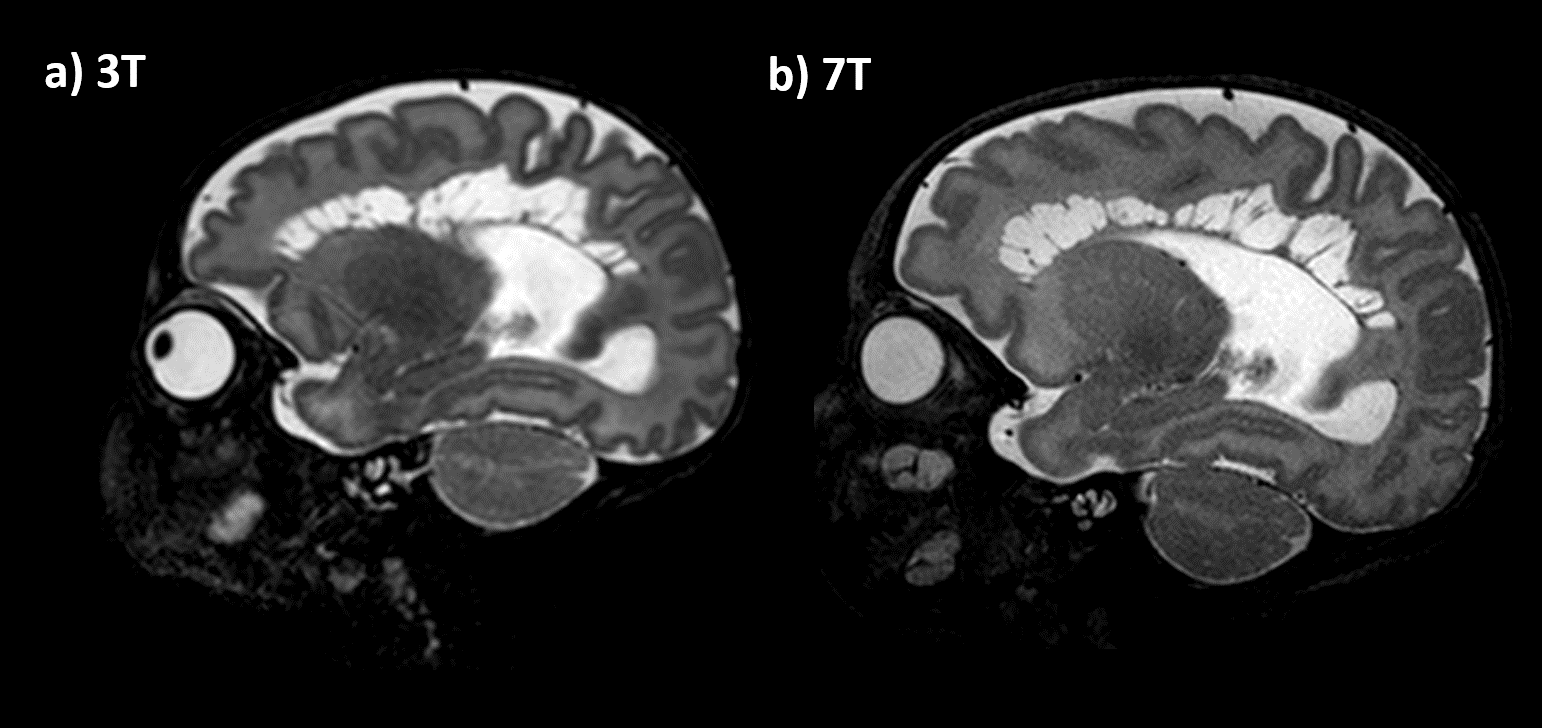

Across the cohort, additional detail of anatomical or pathological features were seen in the 7T scans compared to typical 3T scans. In all 7 participants, image quality of the 7T scans was observed to be equivalent or superior to 3T scans. These included: specific improvements in visualisation of the hippocampus, cerebellum vermis and cortical folding of the occipital lobe, (Figure1). 7T was also able to demonstrate pathologies and offered more information than 3T, such as improved visualization of cystic septi in periventricular leukomalacia (PVL)(Figure2).

Figure 1: 7T (a-c) and 3T (d-f) T2W images of a 40+1 week male newborn infant (a, d) and 41+1 week female newborn infant (b,c,e,f). Note the clearer depiction of the hippocampus in 1a compared to 1d, of the cerebellum vermis in 1b than 1e, and improved overall cortical folding in occipital lobe in 1c than 1f.